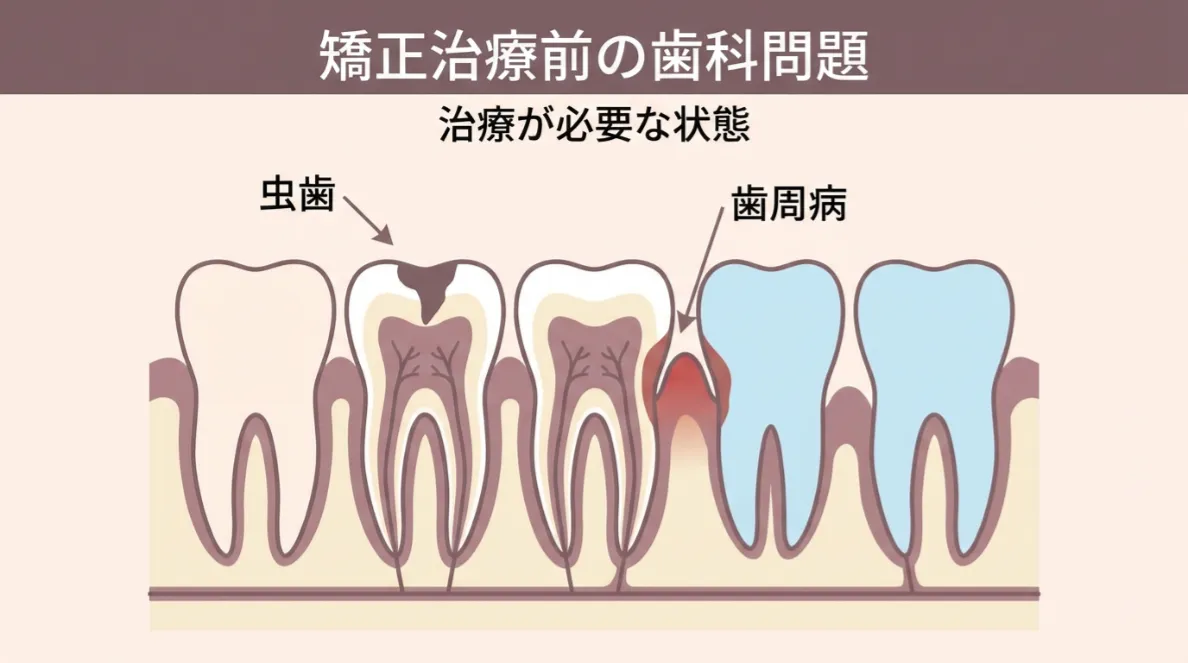

歯周病や虫歯が進行している方

歯ぐきに炎症があると、矯正の力がうまく伝わらず、痛みが出やすくなります。まずは治療でお口の環境を整えることが大切です。

むし歯や歯周病があってもできますか?

軽度のむし歯や歯ぐきの炎症がある場合は、治療を終えてから矯正を始めることで安全に進められます。当院では、一般歯科・歯周治療・矯正治療をすべて同じ院内で行える体制があるため、複数の医院を行き来する必要がありません。